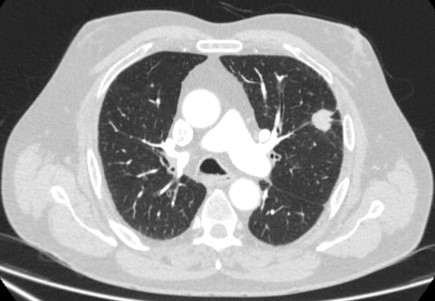

Computed tomography (CT) showing a left upper lobe peripheral nodule with several pleural ‘tags’ and element of retraction of the adjacent pleura. Resection histopathology confirmed a well-differentiated squamous cell lung cancer

From the collection of Dr George Tsaknis, MD, PhD, FRCP(London), MRQA, MAcadMEd, PGCert; used with permission